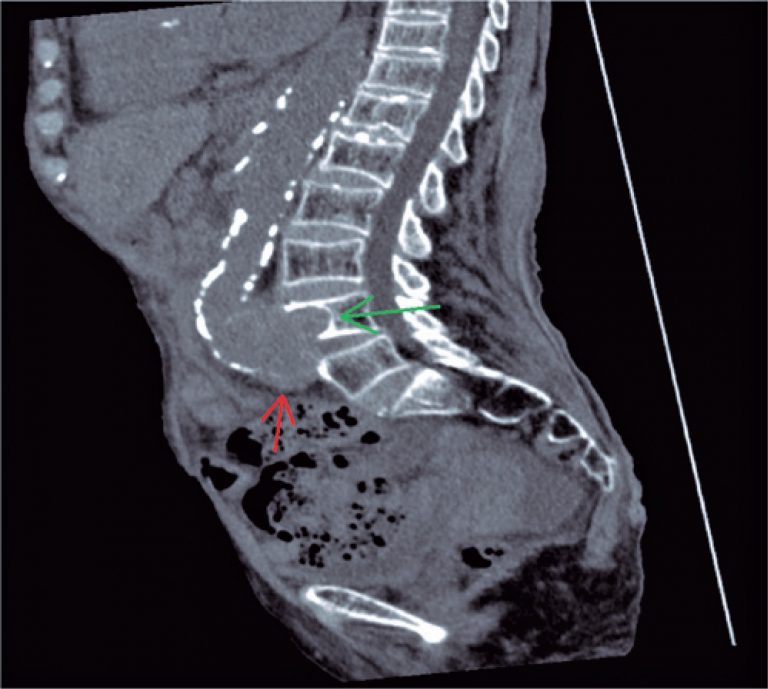

Os cortes da tomografia computadorizada ( e ) evidenciaram aneurisma fusiforme da bifurcação aortoilíaca, que se estendia à artéria ilíaca comum direta. Este aneurisma determinava erosão do aspecto anterior do corpo vertebral de L4, com remodelamento ósseo, marcado por esclerose cortical subjacente.